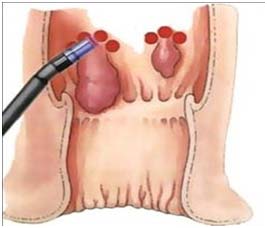

بستن شریان هموروئید با استفاده از داپلر

در این روش با استفاده از داپلر عروق تغذیه کننده هموروئید مشخص شده و بسته میشود .این عمل باعث قطع جریان خون هموروئید شده و تورم ان از بین میرود.ریت درمانی ان کمتر و عوارض ان نیز نسبت به جراحی کمتر است.

در مراحل اولیه همورویید وقتی همورویید خیلی بزرگ نشده ودچار عارضه نیست میتوان از لیزر درمانی کمک گرفت.این نوع لیزرها یک وسیله ی مخصوص دارد که وارد مقعد شده و به جهات مختلف تابانده میشود و باعث کاهش علایم هموروئید میشود.لیزر موجب میشود هم درد ان کمتر شده و هم اندازه ی ان کوچکتر میشود.از این نوع لیزر نمیتوان در درمان هموروئیدهای خیلی بزرگ و دچار عارضه سود برد.

۱-در یک روش پروب لیزر روی هموروئید داخلی گذاشته میشود.اشعه مادون قرمز تابانده شده و جای تابش سفید رنگ میشود،این طول موج توسط هموگلوبین جذب بالایی دارد و باعث انعقاد عروق داخل هموروئید میشود.پاکه هموروئید پس از چند روز کوچک شده و از بین میرود.این روش نیاز به بیهوشی وحتی بی حسی نداردو فقط برای همورویید داخلی کاربرد دارد

۲-در این روش از فیبر دیود استفاده میشود؛به این صورت که فیبر حامل اشعه وارد پاکه هموروئید شده اشعه تابانده میشود عروق داخل همورویید لخته شده و پاکه هموروئید از بین میرود.قیمت این نوع لیزرها گران میباشد

لیزرهای پرتوان دی اگسید کربن- co2

با این نوع لیزر تمام انواع هموروئید را میتوان درمان نمود.این لیزر پر توان بوده و با کمک ان میتوان پاکه هموروئید را بطور کامل برداشت.در واقع این لیزر کار چاقوی جراحی را انجام میدهد واین بیماری را بطور کامل درمان میکند.